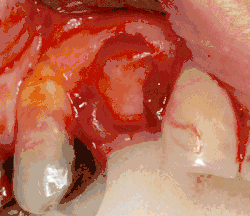

Additional procedures to augment deficient bone in implant site

For an implant to osseointegrate, it needs to be surrounded by a healthy quantity of bone. In order for it to survive long-term, it needs to have a thick healthy soft tissue (gingiva) envelope around it. It is common for either the bone or soft tissue to be so deficient that the surgeon needs to reconstruct it either before or during implant placement.[50]: 1084 All techniques of augmenting the alveolar bone in preparation for implant placement are invasive and associated with a degree of morbidity.[59]

Hard tissue (bone) reconstruction

Bone grafting is necessary when there is a lack of bone. It also helps to stabilize the implant by increasing survival rates of the implant and decreasing marginal bone level loss.[60] While there are always new implant types, such as short implants, and techniques to allow compromise, a general treatment goal is to have a minimum of 10 mm (0.39 in) in bone height, and 6 mm (0.24 in) in width. Alternatively, bone defects are graded from A to D (A=10+ mm of bone, B=7–9 mm, C=4–6 mm and D=0–3 mm) where an implant's likelihood of osseointegrating is related to the grade of bone.[61]: 250

To achieve an adequate width and height of bone, various bone grafting techniques have been developed. The most frequently used is called guided bone graft augmentation where a defect is filled with either natural (harvested or autograft) bone or allograft (donor bone or synthetic bone substitute), covered with a semi-permeable membrane and allowed to heal. During the healing phase, natural bone replaces the graft, forming a new bony base for the implant.[56]: 223

Soft tissue (gingiva) reconstruction

The gingiva surrounding a tooth has a 2–3 mm band of bright pink, very strong attached mucosa, then a darker, larger area of unattached mucosa that folds into the cheeks. When replacing a tooth with an implant, a band of strong, attached gingiva is needed to keep the implant healthy in the long-term. This is especially important with implants because the blood supply is more precarious in the gingiva surrounding an implant, and is theoretically more susceptible to injury because of a longer attachment to the implant than on a tooth (a longer biologic width).[64]: 629–633

When an adequate band of attached tissue is absent, it can be recreated with a soft tissue graft. There are four methods that can be used to transplant soft tissue. A roll of tissue adjacent to an implant (referred to as a palatal roll) can be moved towards the lip (buccal), gingiva from the palate can be transplanted, deeper connective tissue from the palate can be transplanted or, when a larger piece of tissue is needed, a finger of tissue based on a blood vessel in the palate (called a vascularized interpositional periosteal-connective tissue (VIP-CT) flap) can be repositioned to the area.[58]: 113–188 Xenogeneic collagen matrices are used for gingival augmentation after dental implantation.[65][66]

Additionally, for an implant to look esthetic, a band of full, plump gingiva is needed to fill in the space on either side of implant. The most common soft tissue complication is called a black triangle, where the papilla (the small triangular piece of tissue between two teeth) shrinks back and leaves a triangular void between the implant and the adjacent teeth. Dentists can only expect 2–4 mm of papilla height over the underlying bone. A black triangle can be expected if the distance between where the teeth touch and bone is any greater.[50]: 81–84